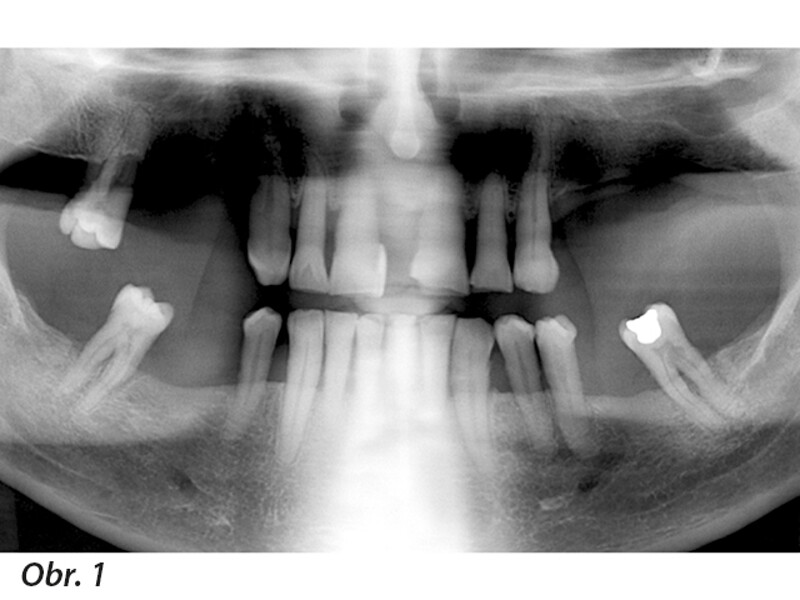

Plně digitální Pro Arch protokol